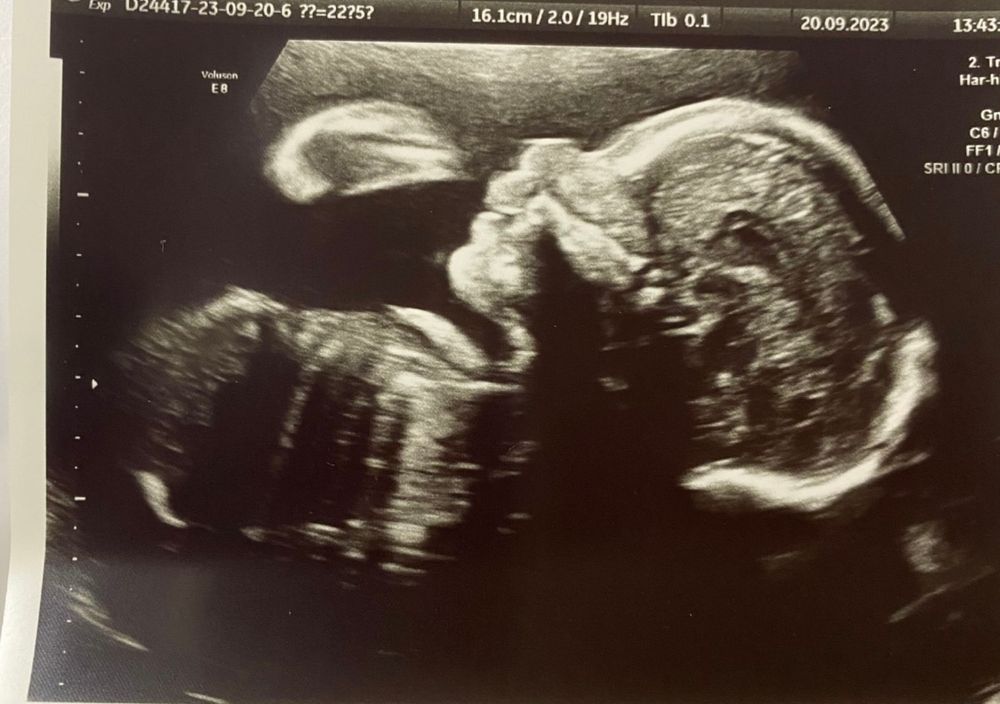

Витаминка, на 3д была у генетиков, третья дочка похожа на мою среднюю трехлетку) даже не сказала бы что там микро нос. Как сказали в ЦПСИР «нос просто пока не окостенел и там хрящик». Но я такой человек у меня слишком много вопросов и ожидание , особенно такое меня выматывает. Врач мне когда отдавала снимок сказала «держите вашу хорошую ляльку и не грустите»